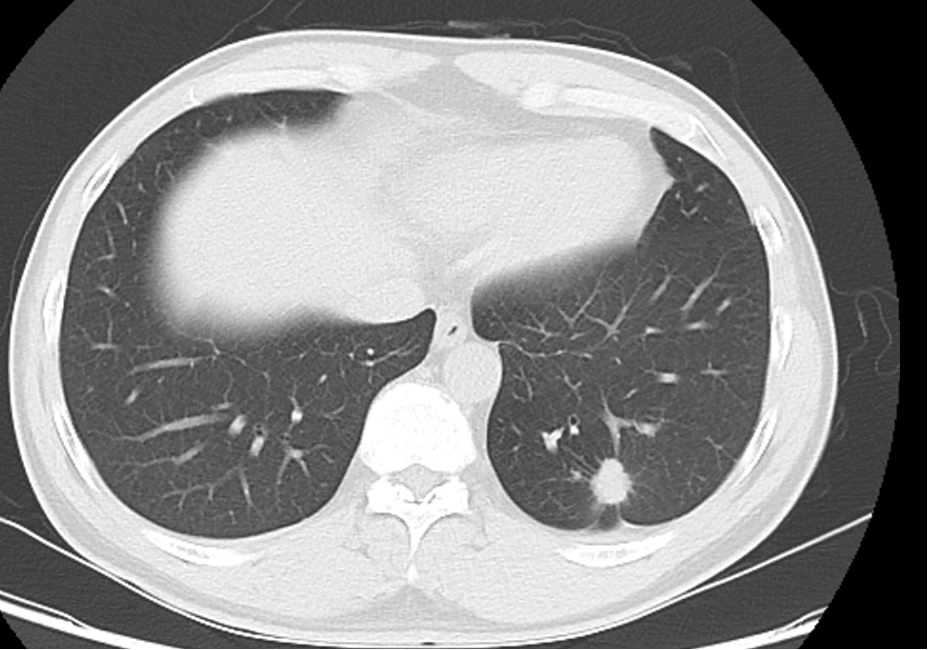

上周,我收治了一位42岁男性患者,因体检发现左下肺结节4月余入院。4个月前行胸部CT检查发现“左下肺结节,大小约17mm x15mm,边缘毛糙,见分叶征、毛刺征及胸膜凹陷征,考虑肺癌,建议手术治疗。因个人原因,推迟手术。本次复诊,行胸部CT示左下肺结节有增大,大小约19*16mm,有恶性肿瘤征象,根据AJCC第八版肺癌TNM分期,目前临床诊断考虑左肺下叶肺癌 cT1bN0M0 IA2期,根据NCCN2020肺癌指南,建议行肺癌根治术。

图2:术前胸部CT肺窗

术前检查无手术禁忌,行单孔胸腔镜左下肺切除,术中冰冻病理提示左下肺浸润型腺癌,行肺癌根治清扫纵隔淋巴结,术后病理纵隔淋巴结未见转移。术后第2天拔除胸管,术后3天出院,这周来门诊复查肺膨胀好,患者无不适主诉。术后病理诊断pT1bN0M0 IA2期,不需要术后辅助治疗,只需定期随访复查。